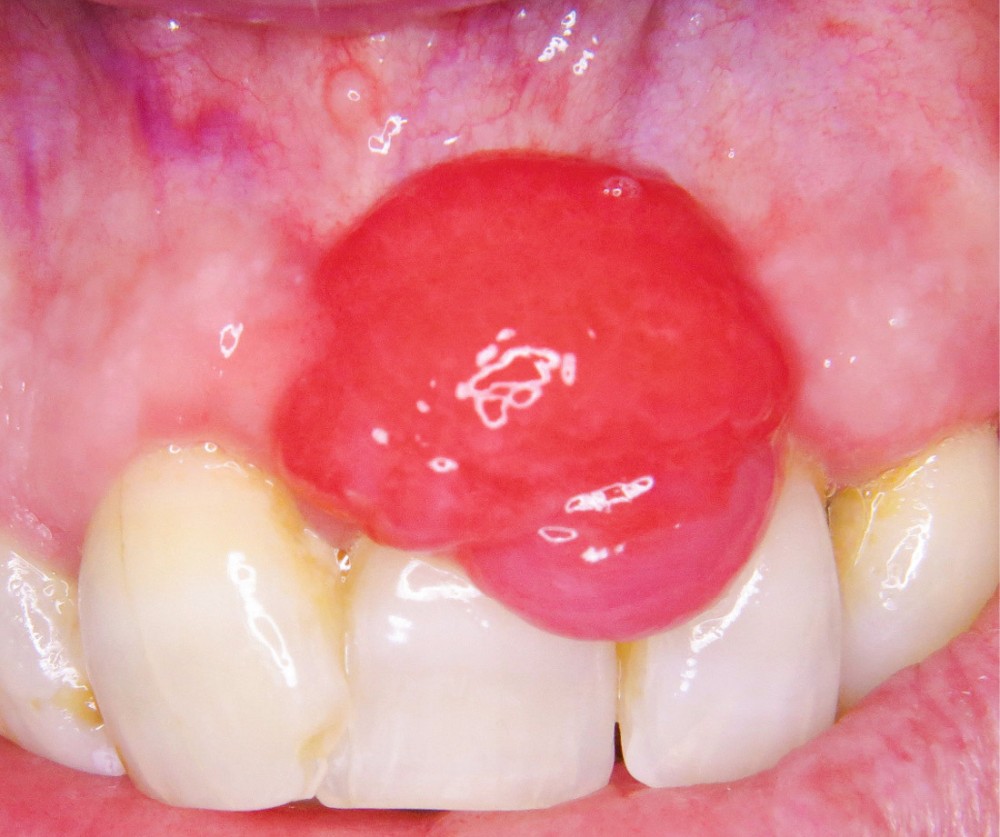

1. Épulis inflammatoire (plasmocytaire)

- Nodule indolore, pédiculé, érythémateux, parfois ulcéré (fig. 1a).

- Forme gravidique fréquente au 2e et 3e trimestres (fig. 1b). Favorisée par l’augmentation du taux de progestérone, œstrogènes, prostaglandines entraînant une vasodilatation.